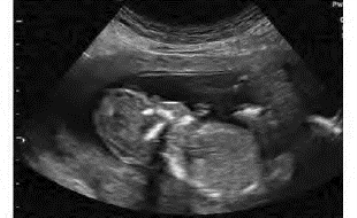

1.38.5五、多胎妊娠